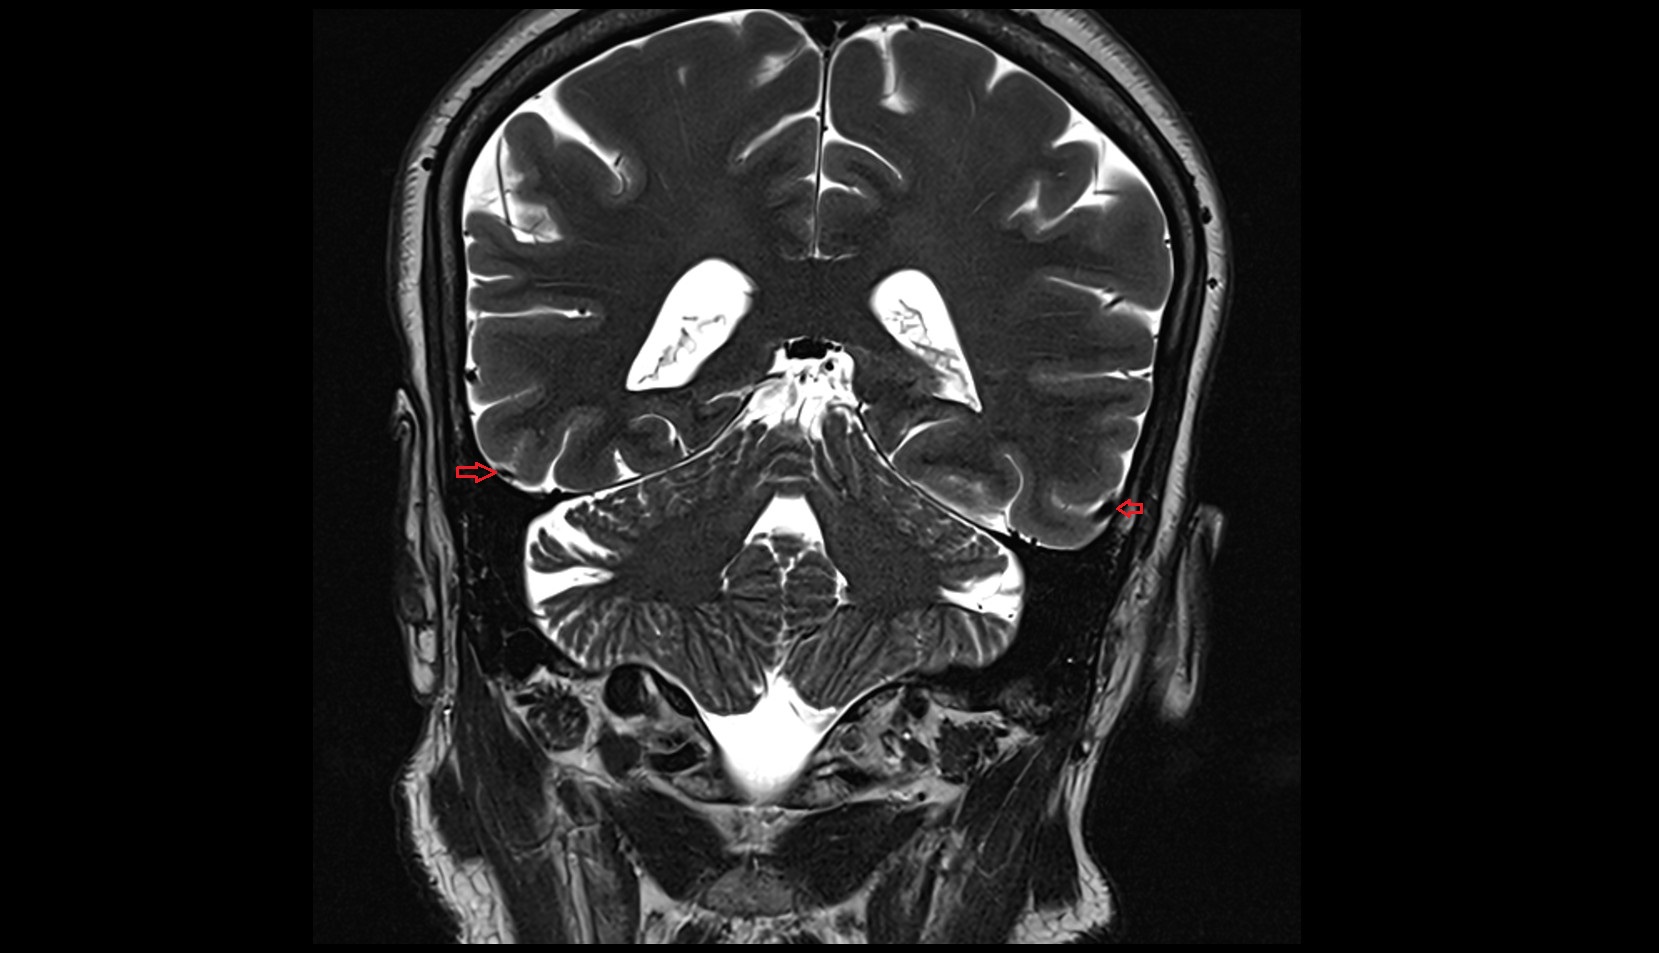

Inferior anastomotic vein (Labbé) MRI 3T coronal image